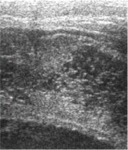

Рисунок 4. Тот же ребенок, осмотр

через 1 месяц после травмы.

| а - нейросонография, В-режим, правая парасагиттальная плоскость. Определяется

резкая дилятация визуализируемых фрагментов бокового желудочка, структура мозговой

ткани нарушена |

б - то же, фрагмент. Определяется деструкция мозговой ткани с образованием

множественных кистозных полостей мелких размеров (энцефаломаляция) |

в - тот же ребенок, фронтальная плоскость сканирования. Очаги энцефаломаляции

определяются в обоих полушариях |

г

- допплерография на средней мозговой артерии - показатели периферического сопро-тивления

в пределах возрастной нормы. г

- допплерография на средней мозговой артерии - показатели периферического сопро-тивления

в пределах возрастной нормы. |